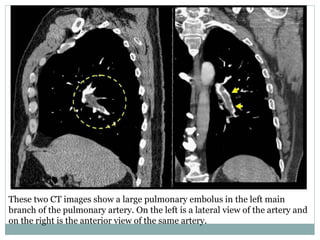

These two CT images show a large pulmonary embolus in the left main

branch of the pulmonary artery. On the left is a lateral view of the artery and

on the right is the anterior view of the same artery.